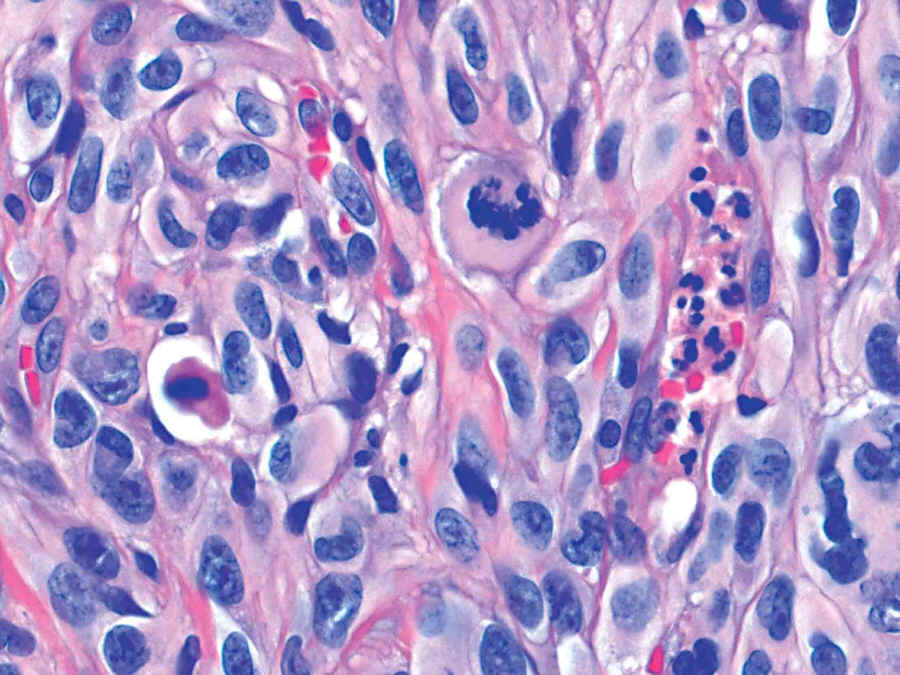

Case #3

81 year old man with a 2 cm red nodule in the skin of the face.